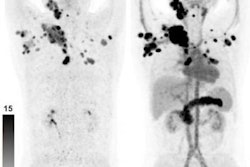

Contrast-enhanced CT (ceCT) and FAPI-PET/CT (68Ga-FAPI-PET) images from the same patient with local disease recurrence. In contrast to CT, FAPI-PET/CT discriminates a metastatic lymph node from the local recurrence mass (red arrow). FAPI-PET/CT also reveals possible new liver (yellow arrows) and bone (blue arrows) metastases. Images courtesy of Journal of Nuclear Medicine."In all cases, changes in staging were caused by the detection of new or additional distant metastases in one or more organ systems," the authors added. They also found a "markedly elevated uptake" of Ga-68-FAPI in most PDAC patients as soon as one hour after administration.

"Analyses of tracer biodistribution demonstrated a high FAPI uptake in primary PDAC as well as lymph nodes and distant metastases, whereas healthy tissues have negligible background activity," they wrote. "This leads to excellent tumor/background ratios for PDAC, similar to those shown by previous studies on FAPI-PET/CT in PDAC and other tumors."